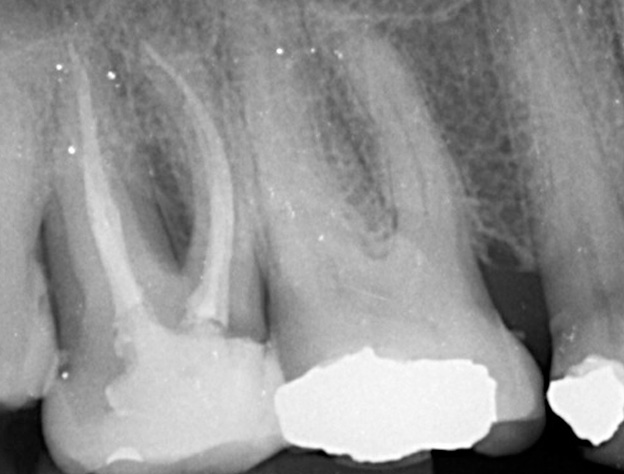

Gallery - Root Canal Treatment

Case 3

Before After